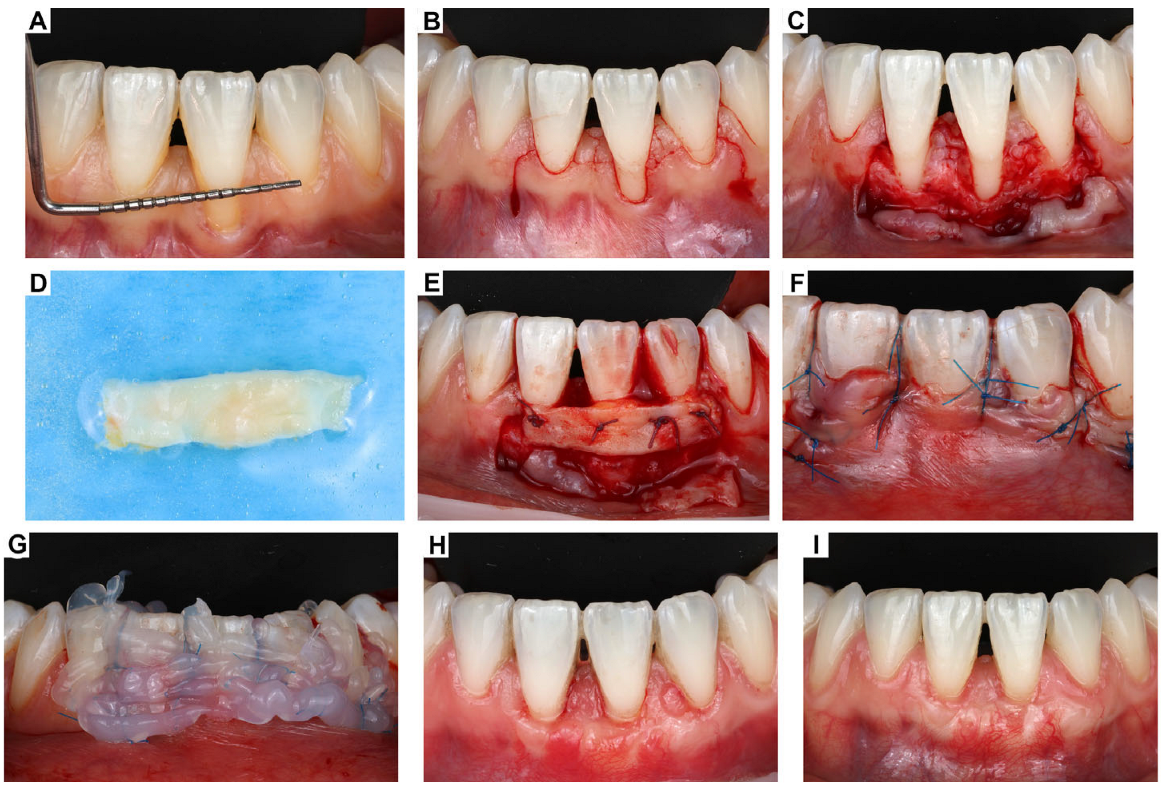

2. Clinical Case Presentation of Complex Periodontal Surgery

Case Report-1